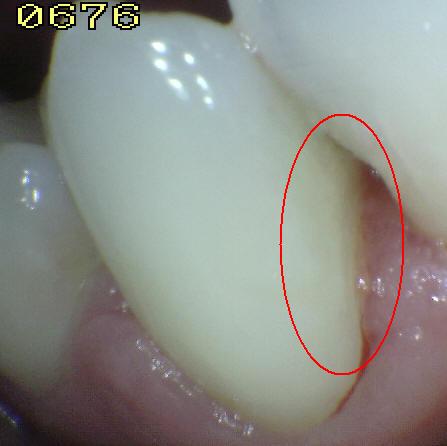

El ICCMS clasifica radiográficamente las superficies

posteriores de los dientes (36,37) Se

ha reportado que tanto la reproducibilidad como la precisión

de este sistema de clasificación son de significativas (33)

a excelentes (37)

La evidencia

indica que la profundidad de penetración radiográfica en la

que se puede predecir de forma confiable que la superficie

del diente está cavitada y que la dentina está muy

infectada, es cuando la radiolucidez está más alla del

tercio externo de dentina (7,34,35,38,40).

Esto corresponde a los códigos 4, 5 y 6 en el sistema de

clasificación radiográfica de ICCMS. Ver tabla 6. En casos en que las

tasas de progresión son rápidas, se puede esperar que en

lesiones con clasificación 3 en el sistema descrito

anteriormente, haya formación de cavidad.